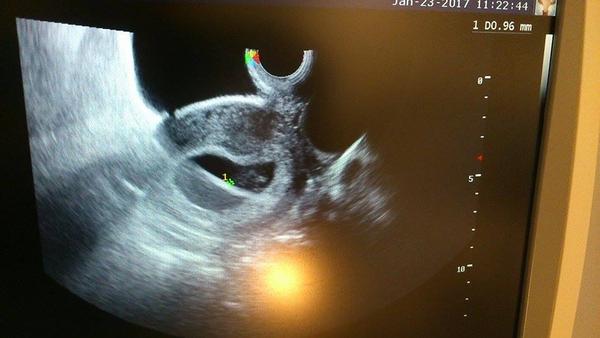

@luta13 ahojik zatial mam tieto dve o 2 týždne pošlem znovu a dakujem moc pekne snažim sa a moc tešime

@luta13 dakujem hned ju sem pošlem a tiež sa tešim ako to rastie 👶